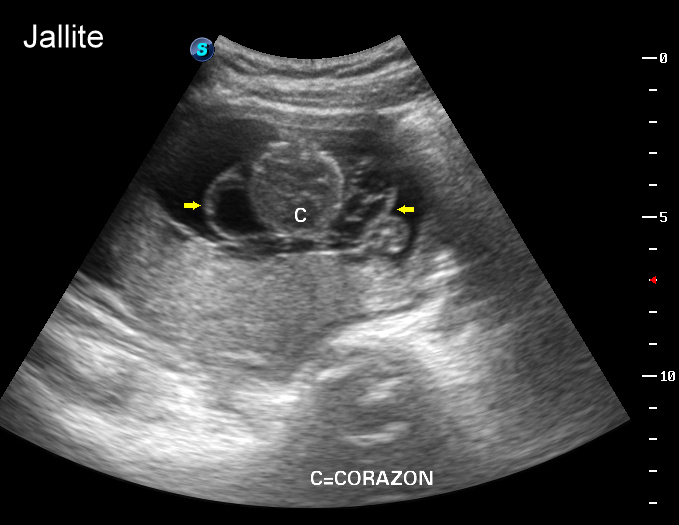

Ecografia 2D 11 semanas Higroma quistico pliegue nucal patologico Dr. Rafael Ortega Muñoz

HIGROMA QUISTICO MEDICINA FETAL PERÚ YouTube

Higroma quístico del primer trimestre Diagnóstico de hernia diafragmática congénita